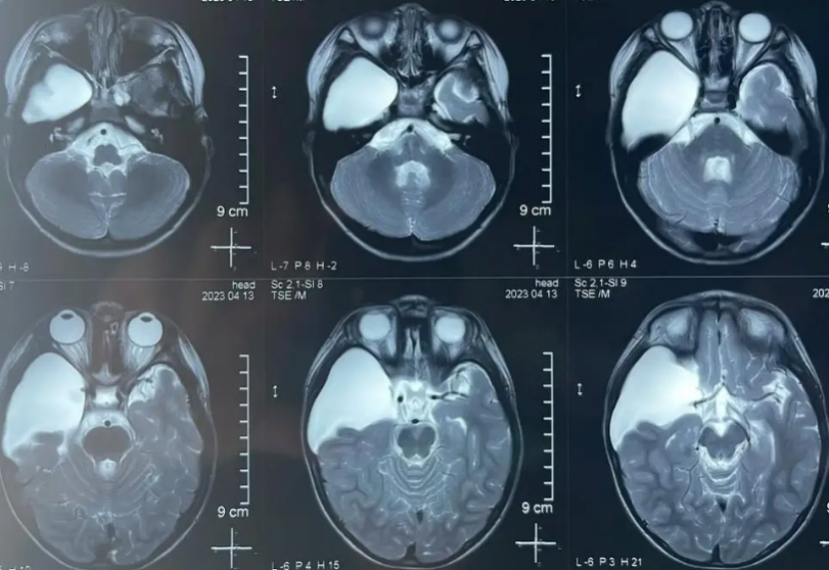

颅中窝囊肿可导致偏瘫蛛网膜囊肿的诊断常规应用CT和MRI检查一般可以确诊,仅在少数情况下针对中线部位鞍上和后颅凹病变,应用脑脊液对比剂或流量测定检查。1)CT:表现为边界光滑、无钙化的脑实质外囊性肿物,密度类似脑脊液。静脉注射对比剂无强化。2) MRI:在鉴别蛛网膜囊肿内容物与肿瘤囊液方面优于CT,并可显示囊种壁。

MRI